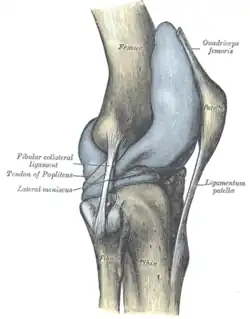

Seitliche Bandsicherung

Das Knie hat zwei Seitenbänder: ein inneres (Ligamentum collaterale tibiale) und ein äußeres (Ligamentum collaterale fibulare). In Streckstellung sind beide Seitenbänder (auch Kollateralbänder genannt) gespannt und verhindern somit die Drehbewegung, in Beugestellung verkleinert sich der Krümmungsradius, Ursprung und Ansatz nähern sich einander an und die Bänder sind infolgedessen entspannt. Beide Seitenbänder stabilisieren das Kniegelenk in seitlicher Richtung (Frontalebene), damit ein Wegknicken in eine O-Bein-Stellung (Genu varum) oder X-Bein-Stellung (Genu valgum) verhindert wird.

Das Außenband (Ligamentum collaterale fibulare bzw. laterale) ist ein kräftiges Band, das in seinem dorsalen Abschnitt zylinderförmig vom Aufsatz des seitlichen Oberschenkelknochens (Epicondylus lateralis femoris) zum Wadenbeinkopf (Caput fibulae) zieht. Es hat keine feste Verbindung zur Gelenkkapsel und den Menisken.

Das 2013 beschriebene anterolaterale Ligament zieht vom gleichen Ursprung wie das Außenband zum anterolateralen Schienbein und ist dort mittig zwischen Wadenbeinköpfchen und Tuberositas tibiae verwachsen. Zudem ist es fest mit dem Außenmeniskus verbunden.[14]

Hintere Bandsicherung

Auf der hinteren Seite des Kniegelenks finden sich zwei Bänder. Das schräge Kniekehlenband (Ligamentum popliteum obliquum) entspringt an der Ansatzstelle des halbhäutigen Muskels (Musculus semimembranosus) am inneren Schienbeinknorren und verstärkt die hintere Seite der Gelenkkapsel, mit der sie verschmilzt. Das bogenförmige Kniekehlenband (Ligamentum popliteum arcuatum) hingegen zieht vom hinteren Wadenbeinkopf über den Ansatz des Kniekehlenmuskels hinweg und zieht ebenfalls als Verstärker der Kapsel mittig nach oben.

Strecker

Der Oberschenkelknochen wird vorne von einem großen vierköpfigen Streckmuskel (Musculus quadriceps femoris) umfasst. Die drei breiten Muskeln (Musculus vastus medialis, Musculus vastus lateralis und Musculus vastus intermedius), sowie der gerade Muskel (Musculus rectus femoris) bilden diese vier Köpfe. Sie strecken das Knie, indem sie an der Schienbeinbeule ansetzen. Zwischen diesen Muskeln und ihrem gemeinsamen Ansatz, der als Kniescheibenband ausläuft, ist die Kniescheibe eingebettet. Der Streckmuskel (Extensor) setzt also zunächst an der Kniescheibe an. Von dort wird die Kraft über das Kniescheibenband auf den Unterschenkel übertragen.